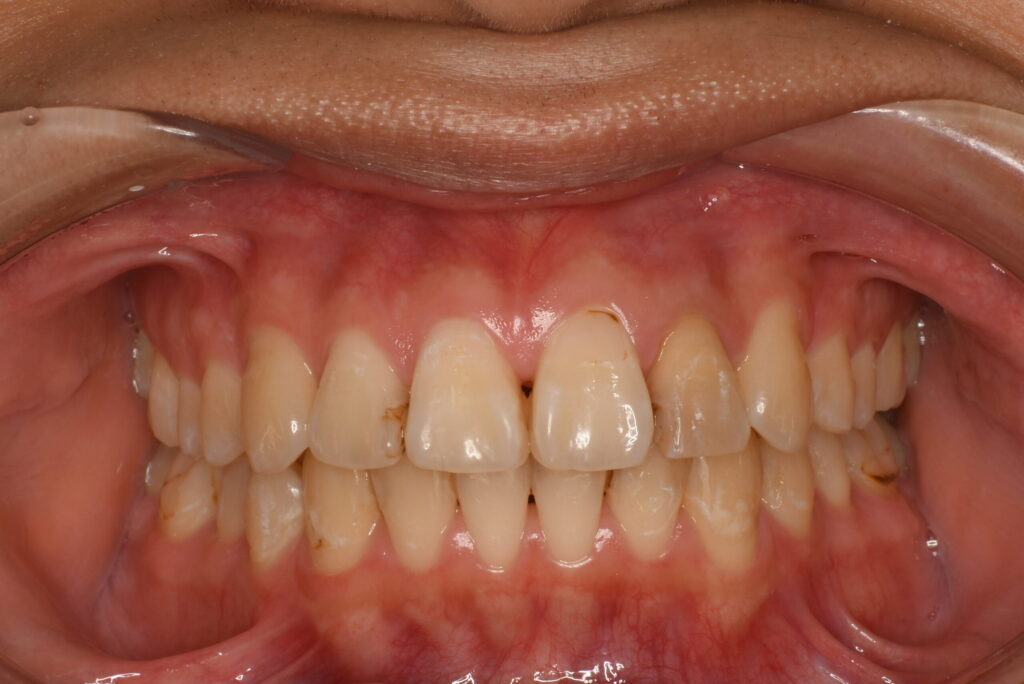

- BEFORE

| 治療内容 | 患者様は、上の前歯の突出や不揃いな歯並びに加え、咬みにくさや歯のサイズ感にも悩まれており、目立たない方法での矯正治療をご希望され来院された。 診査の結果、前歯部の叢生と上顎前突を認めたが、骨格的には非抜歯での矯正が適応可能と判断した。永久歯列期でのインビザラインによる非抜歯矯正を計画した。 治療は、マウスピース型矯正装置「インビザライン」を使用した。歯の移動スペースを確保するため、必要最小限の歯間削合(歯と歯の間をわずかに削る処置)を行い、歯列全体を整えながら、前歯の位置・傾斜を調整した。 また、診査時に歯の表面に脱灰(初期の虫歯)を認めたため、セルフケア指導などの予防処置も並行して実施。歯列の改善とともに、口腔内の健康維持にも配慮した治療を行った。 |